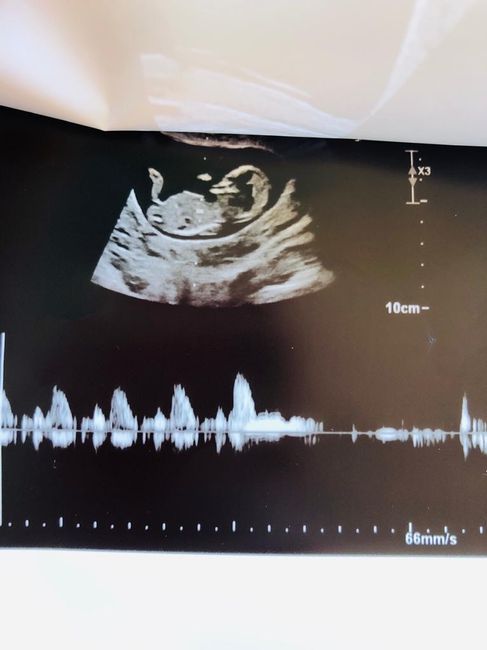

Ciaooo qualcuna ha sentito parlare del metodo Ramzi? A voi ci ha azzeccato o ha sbagliato? Vi metto una foto dell’eco interna a 7+3 “dovrebbe” essere maschio secondo la teoria o sbaglio io a vedere? Altra domandina: l’11 ho fatto il dna fetale (con...